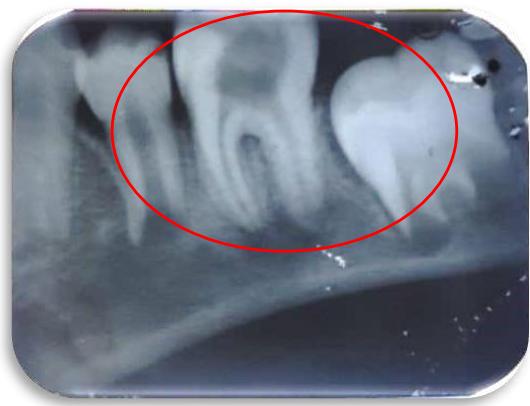

The patient did not respond to any pain stimuli during the examination, confirming the clinical signs of CIPA. Radiographic imaging was performed, which showed deep carious lesions with periapical radiolucency as shown in Figure 3. The diagnosis made was deep carious lesion with periapical abscess w.r.t 46.

Figure 3: Radiolucency involving enamel, dentin and pulp, loss of lamina dura in mesial and distal root, diffused periapical radiolucency with mesial and distal root i.r.t 46